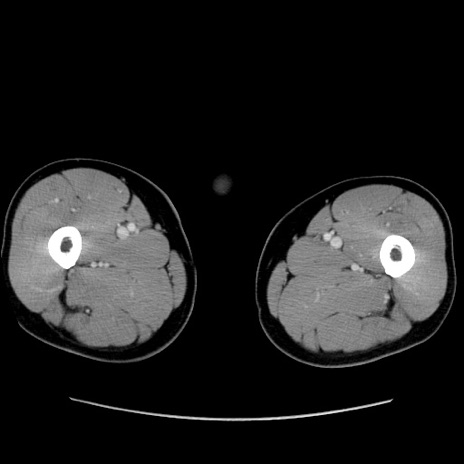

矢状断像

【症例】60歳代 男性

【主訴】右鼠径部膨隆

【現病歴】1年程前より右鼠径部膨隆あり。自己にて還納可能だったため放置していた。3時間前より右鼠径部の脱出を認め、還納困難となり受診。

【既往歴】高血圧

【身体所見】右鼠径部に小児頭大の膨隆あり。弾性硬であり、用手還納は困難。左鼠径部にも膨隆を認める。脱出はなし。

【データ】WBC 15500、CRP 測定なし